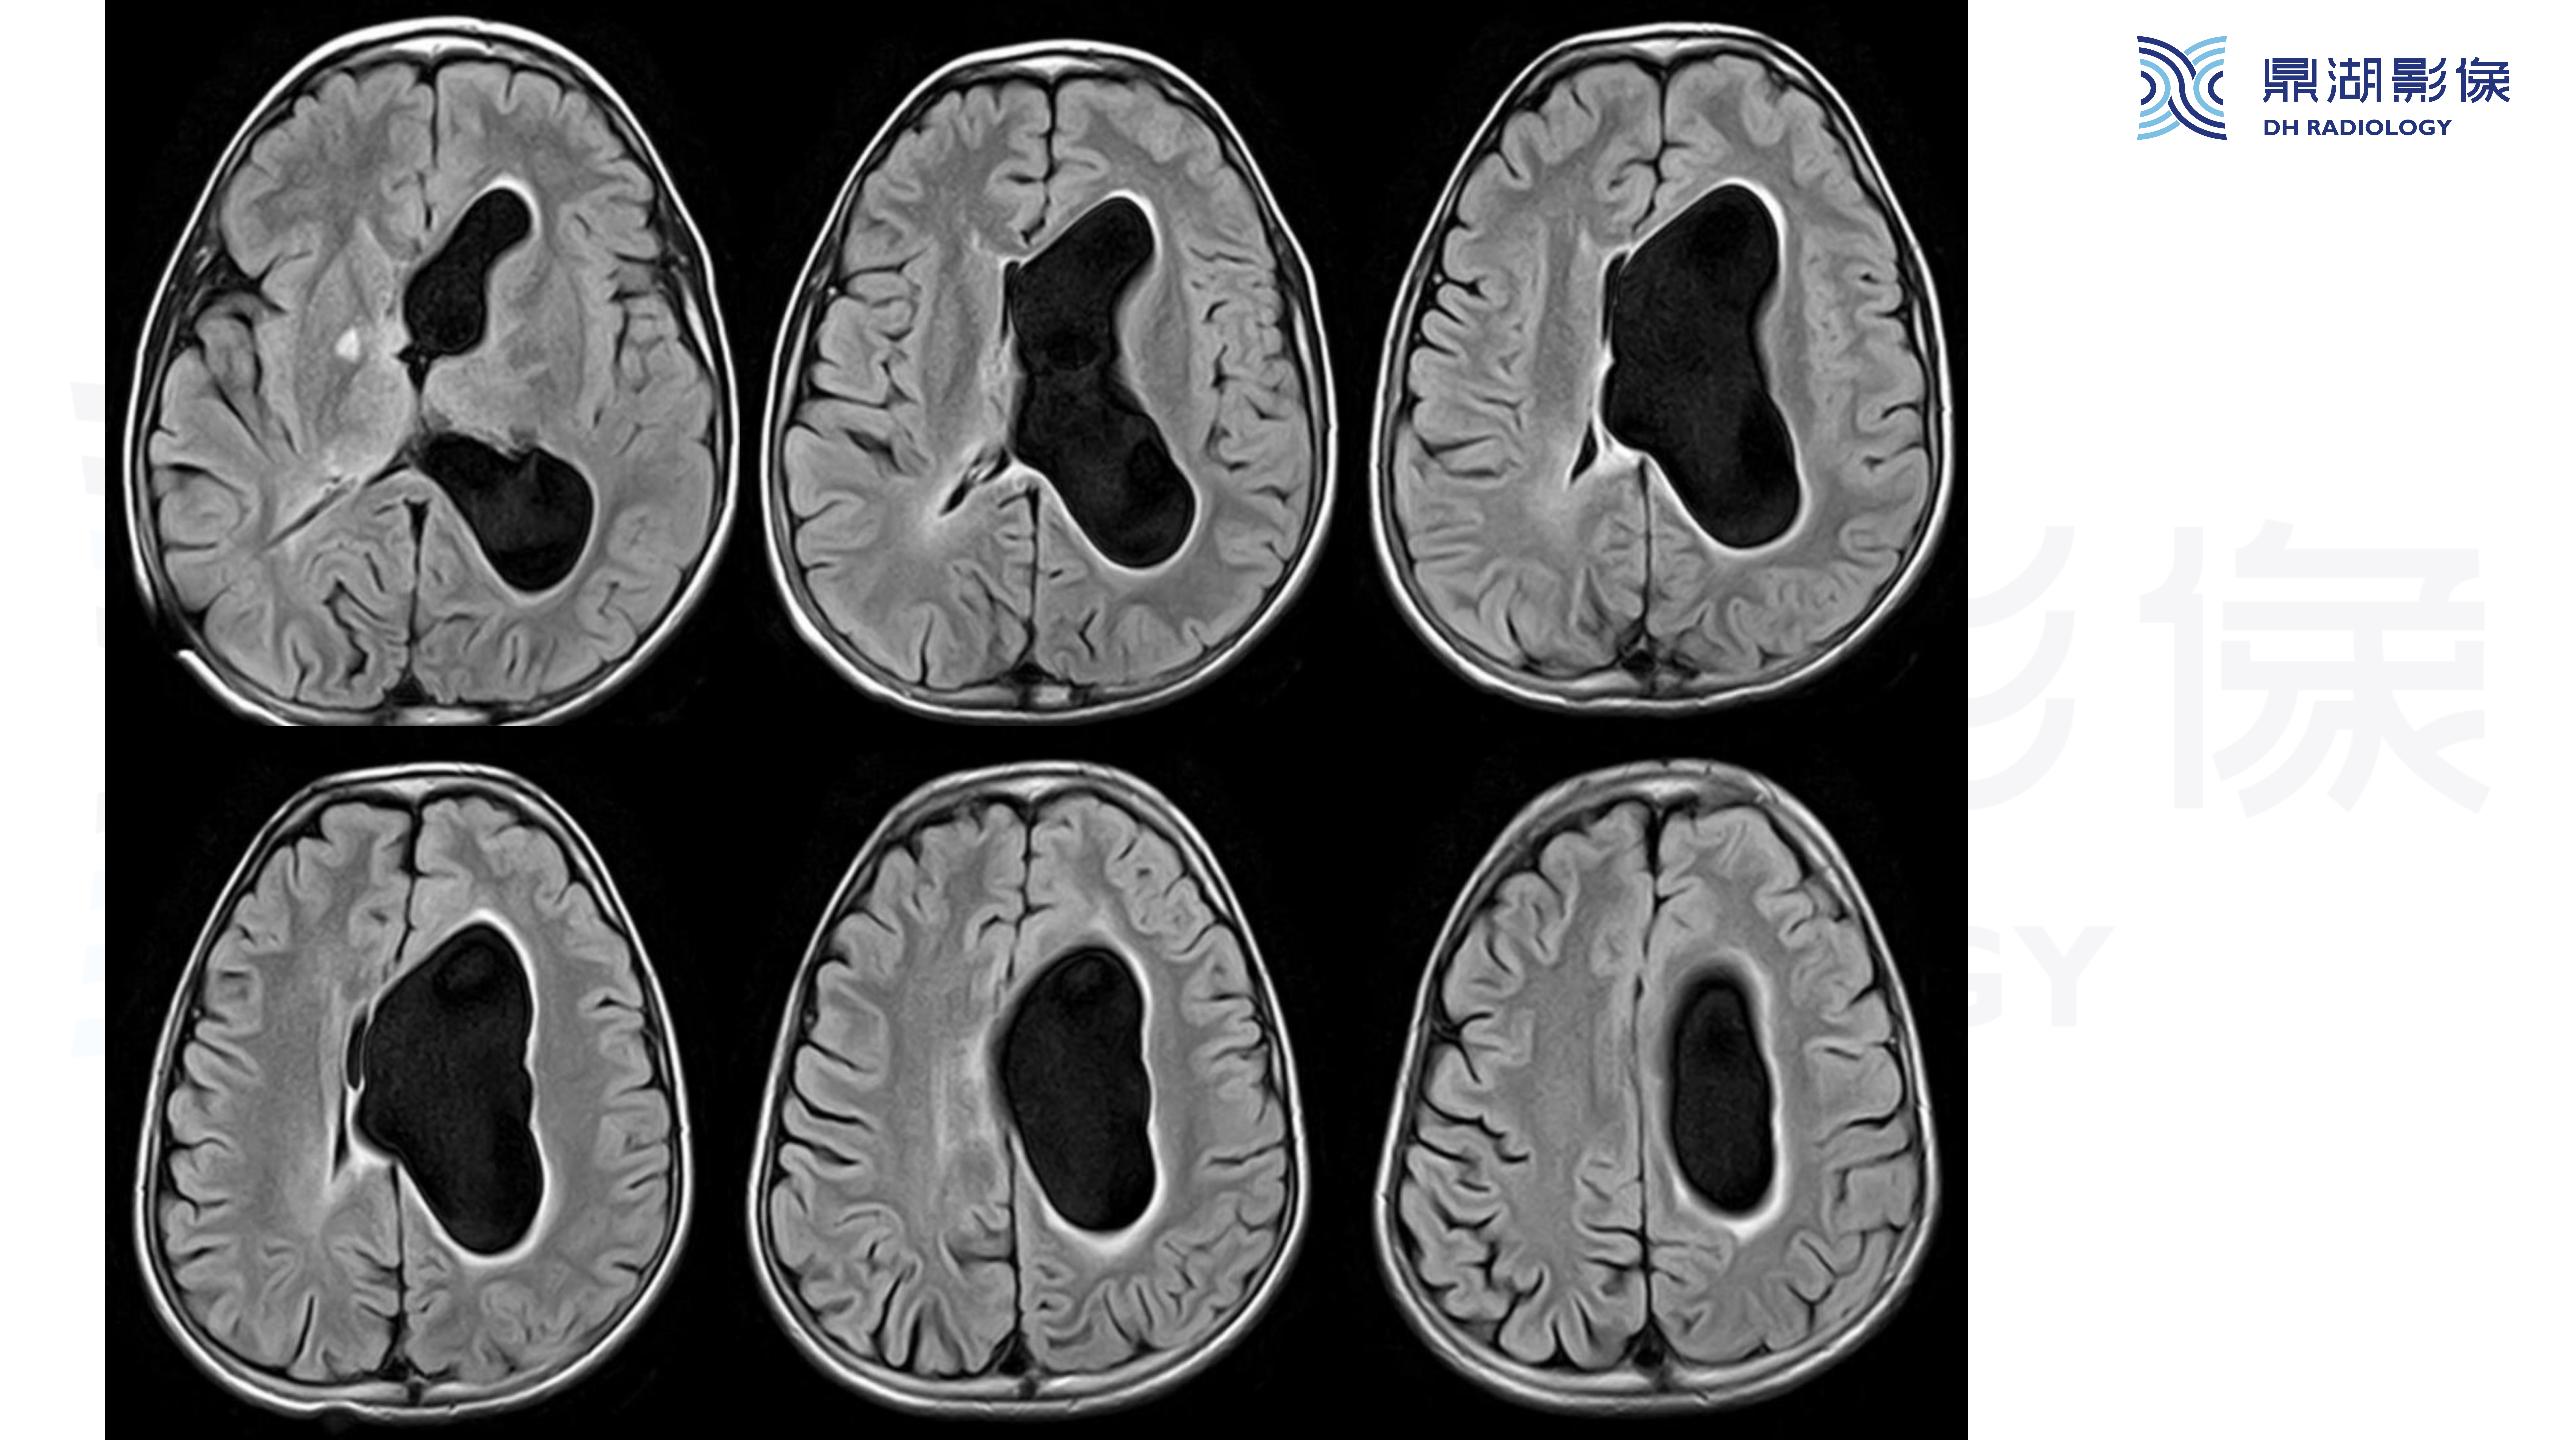

裂隙脑室综合征 (slit ventricle syndrome,SVS)-鼎湖社群读片病例